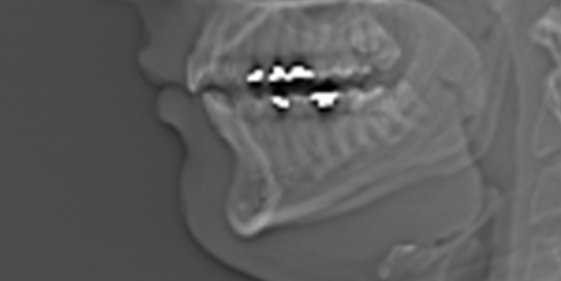

Surgery advice needed

Based on the scan what surgery/surgeries do I need to improve my side profile? (24 years old)looksmax.org

Anyway, you're hyper fixated on the maxilla part, so let's talk about that. Now, for some reason I can't see his pics (they don't load anymore) but to my memory he wasn't very projected sub LF1 line.

Well but have you seen his lf1 area? or lower maxilla? it doesn't require more projection, he has an overbite which means that his lower maxilla is more projected than the mandibleAnd in that sense, by going off of facial depth theory, his maxilla could be better developed / more projecting sub lf1

Really? Overbite? Again idk why but I cant see the images, they dont load for me rn. But I remember it looked like class 1.Well but have you seen his lf1 area? or lower maxilla? it doesn't require more projection, he has an overbite which means that his lower maxilla is more projected than the mandible

Really? Overbite? Again idk why but I cant see the images, they dont load for me rn. But I remember it looked like class 1.

I did give my reason as to why I believe that he could aesthetically benefit from a DJS (more facial depth). His lips don't project a lot, and his nose could be a bit more upturned (looks down turned rn). Overbite might be an additional (but in this case very minor) reason to justify jaw surgery.Well but again, if it comes to "can" and not "will" then we're in agreement about that but you still haven't justified why he should get lefort.

Well you can ask him to post his full side profile and we can see for real if he requires lower maxillary projection.I did give my reason as to why I believe that he could aesthetically benefit from a DJS (more facial depth). His lips don't project a lot, and his nose could be a bit more upturned (looks down turned rn). Overbite might be an additional (but in this case very minor) reason to justify jaw surgery.

Maybe these photos will help, the first one is the normal look and the second one when doing the mewing + jutting combination. I appreciate the adviceWell you can ask him to post his full side profile and we can see for real if he requires lower maxillary projection.

Yeah, so your jaws are kind of short, but you obviously don't NEED DJS by any means. It depends on the aesthetic you're going for. You don't need the best side profile to be good looking. Look at for example Jorge Del Rio. He doesn't have the most amount of facial depth. I mean he isn't Jordan Barrett for example. However he has other features going for him that make that irrelevant.Maybe these photos will help, the first one is the normal look and the second one when doing the mewing + jutting combination. I appreciate the advice

You see, I was right about his maxillaYeah, so your jaws are kind of short, but you obviously don't NEED DJS by any means. It depends on the aesthetic you're going for. You don't need the best side profile to be good looking. Look at for example Jorge Del Rio. He doesn't have the most amount of facial depth. I mean he isn't Jordan Barrett for example. However he has other features going for him that make that irrelevant.

For your DNA you clearly have good jaw development. So one consideration to take into account is that if you were to get DJS, you would look less like you're from the place that you're from, if that makes sense, and that might not be something that you want.

Your ramus is actually kind of tall, which I couldn't tell in the pics with bad lightning. Maybe you can train your masseters or just get gonial implants (more so for the width, not necessarily more ramus height) just to make your jaw pop a bit more. However that might make your jaw TOO wide for its length, so keep that in mind. I haven't seen your front so idk.

But either way, our bro here hasn't had his wisdom teeth erupted, meaning that they don't fit, meaning = some underdevelopment ANYWAY.